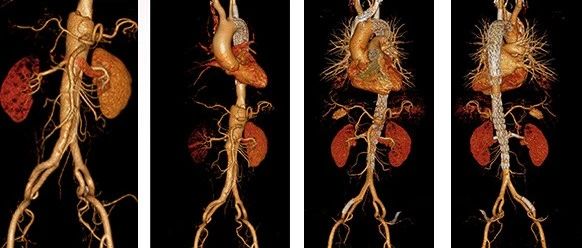

CEC 2022 | 李拥军:主髂动脉闭塞性病变的特点和治疗

2022 CEC 手术精选 | 寇镭:球扩式覆膜支架治疗复杂主髂动脉病变

2022 CEC 手术精选 | 张宏鹏:白塞病合并多发动脉瘤的腔内治疗